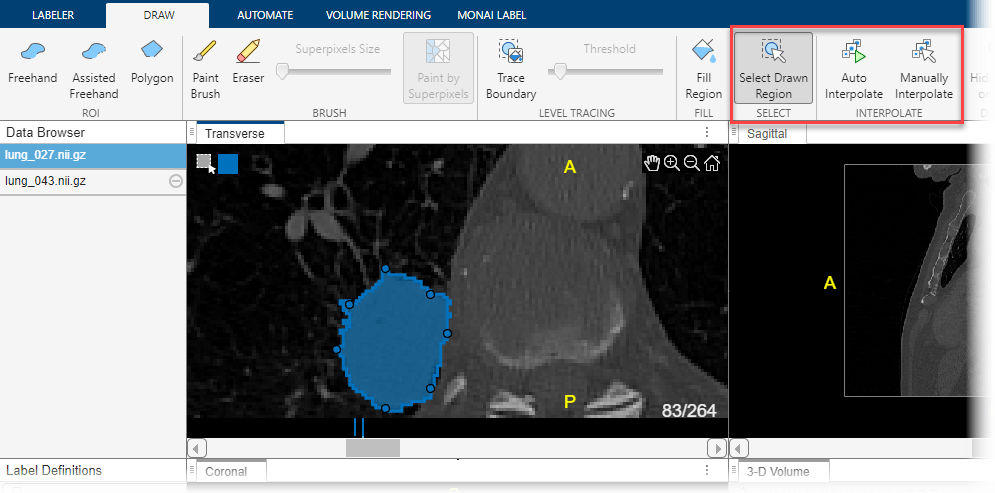

You can move through the image volume and draw labels slice-by-slice. The Medical Image Labeler app also provides interpolation tools in the Draw tab that can help with labeling an object between slices.

To use interpolation, you must first manually label a region on two slices. You have already labeled the tumor in slice 79. Use the same process to label the tumor in slice 83. If the Auto Interpolate button is not active, make sure the labeled region is selected by clicking Select Drawn Region in the app toolstrip and selecting the labeled region.

Click Auto Interpolate. The app automatically labels the tumor in the intermediate slices. The app adds bars above the slider to indicate all the slices that have labeled pixels, which now appears as a solid bar from slice 79 to slice 83.

Alternatively, after labeling an ROI on two slices, you can click Manually Interpolate. With this option, the app opens the Manually Interpolate dialog box. Select the two regions between which you want to interpolate, Region One and Region Two. To select the first region, use the slider at the bottom of the dialog box to navigate to slice 79, and then click inside the labeled tumor. To select the second region, click Region Two, navigate to slice 83, and click inside the labeled tumor. After selecting both regions, click Run to interpolate the label in the intermediate slices.